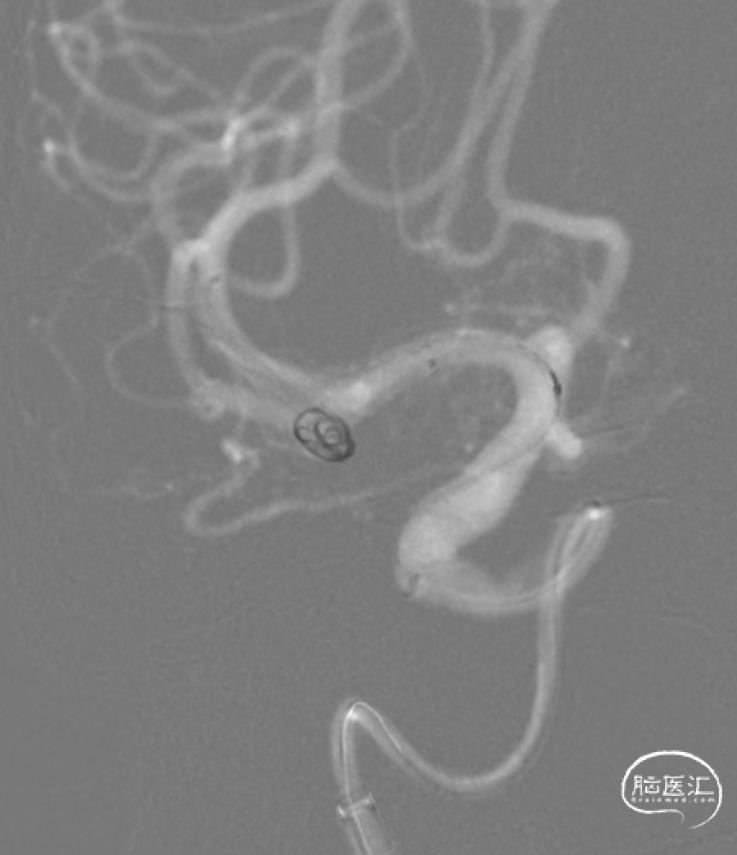

支架导管/支架到位。

拟选用Neuroform Atlas支架,SL-10导管先要到位。

M1主干和分支的角度很刁钻,几乎180°了。但是还好,短时间内快速到位。

输送Neuroform Atlas 3mm×21mm支架到位。

栓塞导管到位。

栓塞导管采用Headway17,相对容易到位。